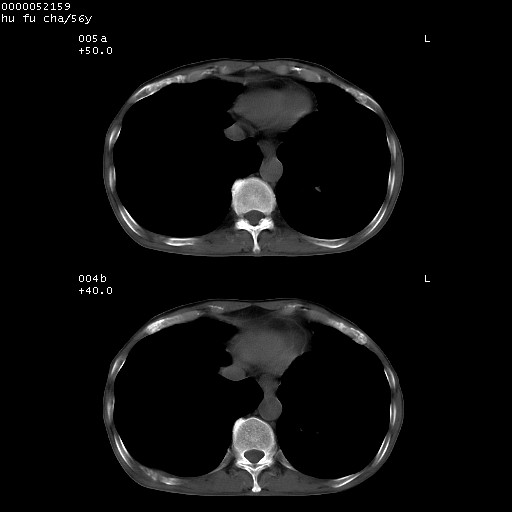

以下是引用zsl6918在2008-8-25 22:47:00的发言:[br]胸骨,胸椎及肋骨均可见多发转移表现,肝内低密度结节不除外转移。原发灶可能在右肺。双侧可见支扩表现。

以下是引用宇宙ct在2008-8-25 23:26:00的发言:[br][br] 胸骨,胸椎及肋骨均可见多发转移表现,肝内低密度结节不除外转移。原发灶可能在右肺。双侧可见支扩表现。 [br] [br]

以下是引用卜一在2008-8-26 8:02:00的发言:[br][br] 支持:肺癌并肺内,胸骨,胁骨,胸椎及肝内转移!另:左肺支气管扩张征伴感染! [br]

以下是引用zjzjr在2008-8-26 11:03:00的发言:[br]支持:肺癌并肺内,胸骨,胁骨,胸椎及肝内转移!另:左肺支气管扩张征伴感染!